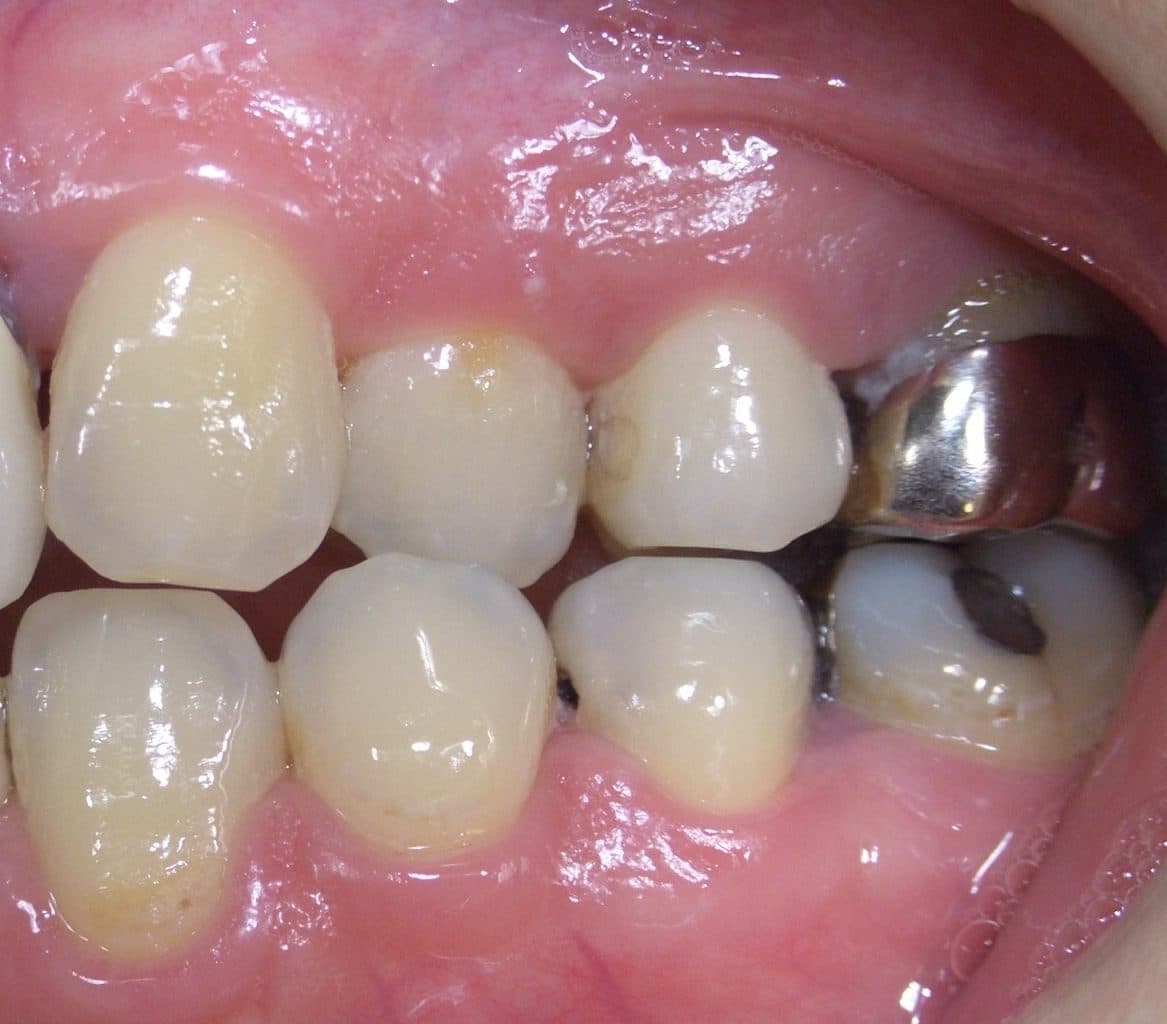

初診の状態です。

金属の被せ物がしてあるのと、セラミック?らしき詰め物がしてあり、

残念ながら、すべて2次虫歯で、痛みもありました。(他にも2次虫歯多数あり。)